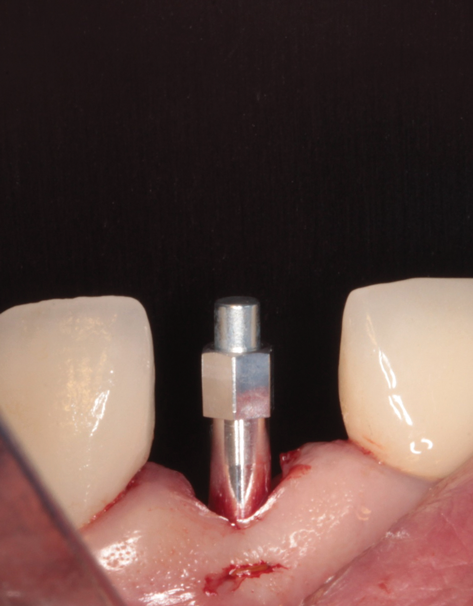

(46.) Occlusal view of the implant after placement.

Figure 46

(47.) The primary stability of the implant was confirmed to be sufficient for immediate loading.

Figure 47